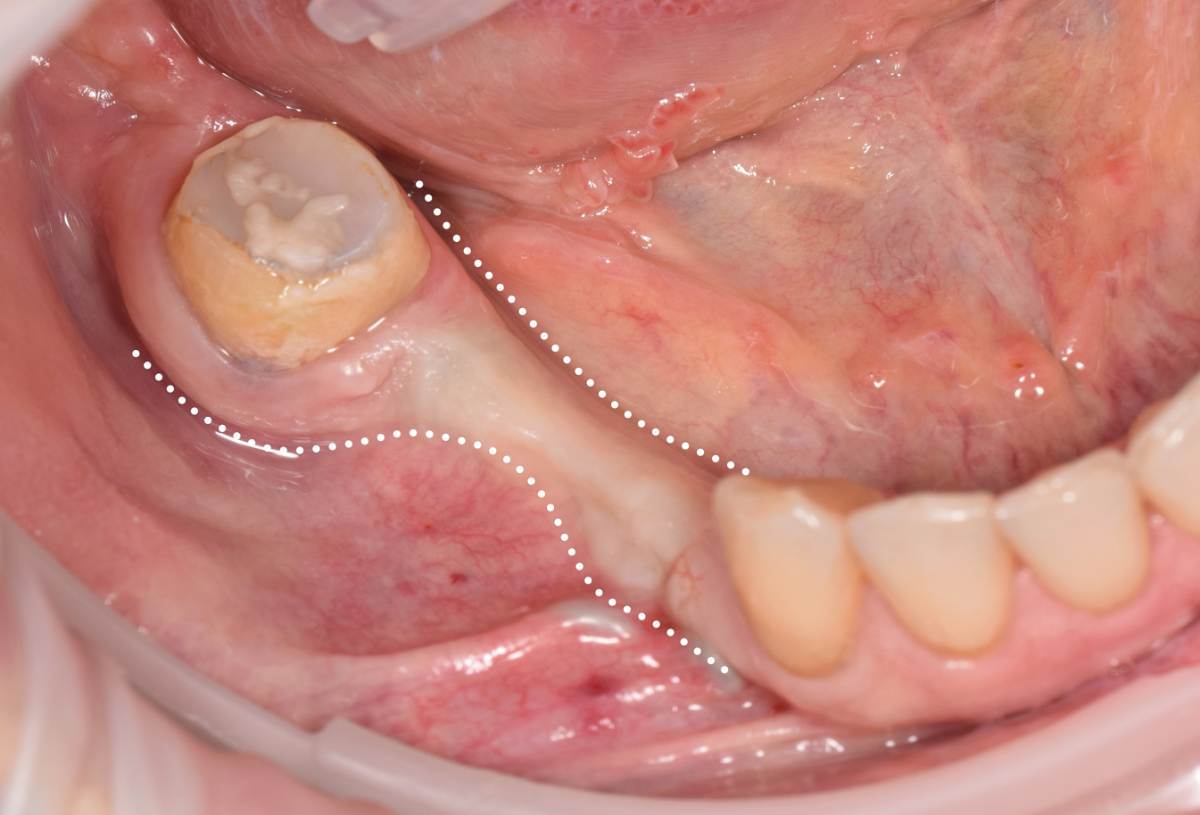

Fin Опубликовано 5 июня, 2025 Поделиться Опубликовано 5 июня, 2025 Здравствуйте коллеги. Хотел бы представить вашему вниманию первую часть кейса по восстановлению 4 сегмента. Перелом зуба 4.5 под мостовидным протезом 4.7-4.4. 4.7 решено оставить до последующего повторного протезирования При планировании имплантации вестибулярное оголение имплантата на 1.5-2мм в области 3. 4. Дефицит керотинизированной слизистой оболочки. Более глубокое положение имплантата приведет к чрезмерному количеству сзизистой оболочки в 7-8 мм. Решено не пытаться использовать ССТ с целью перекрытия оголенного имплантата а попробовать технику морковки профессора Кюри. 1 этап операции. Удаление зуба 4.5, подготовка костного ложа под имплантаты при помощи трепанов и запор костных морковок, установка имплантатов неодент 3.75х10 в позицию 4.4, 4.3х10 в позицию 4.6, ушивание. 2 этап. Создание прикрепленной слизистой. Расщепление лоскута, удаление пиноа, пересадка СДТ с фиксаций его этими же пинами. 3 этап. Открытие имплантатов с установкой ФДМ и снятие швов через 2 недели. Решил не добавлять ССТ. На данный момент ожидаем полное восстановление тканей и приступаем к этапу протезирования. Так как параллельность имплантов достаточна планирую протезировать с уровня имплантатов. 3 2 1 Ссылка на комментарий